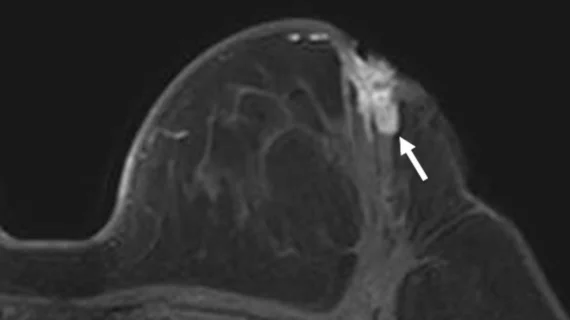

Magnetic resonance imaging (MRI) is the gold standard imaging modality for soft tissues. It produces detail cross-sectional images of soft tissue and bone anatomy, including muscles, tendons, ligaments, brain and organs, without the use of ionizing radiation. In addition to orthopedic imaging, MRI is also used for heart, brain and breast. MRI uses gadolinium contrast in many exams to highlight tissues and blood vessels, which enhances images and offers better diagnostic quality. It can also be used in conjunction with PET scans. How does MRI work? MR creates images by using powerful magnets to polarize hydrogen atoms in water (the body is made of of more than 80% water) so they face in one direction. A radiofrequency pulse is then used to ping these atoms, causing them to wobble, or resonate. The MRI coils detect this and computers can assemble images from the signals. Basic MRI scans will focus on the resonance of fat and water in two different sequences, which highlight and contrast different features in the anatomy.